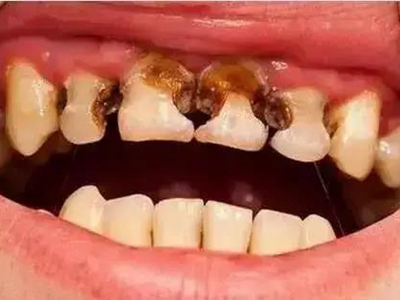

酸蚀症牙齿缺损严重有黑斑图

酸蚀症严重时会使牙齿出现大面积缺损,有三颗下牙损毁严重,露出不整齐的牙骨质边缘,几乎仅余留牙根。缺损处有黑斑,局部呈黄褐色,需积极就医进行牙齿修复。